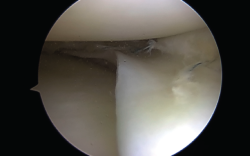

Figura 3. Reducción de una rotura en asa de cubo.

Las roturas periféricas verticales y longitudinales han demostrado buena capacidad para cicatrizar (72 al 94% reportado). Las roturas reparadas en las zonas roja-roja o roja-blanca conducen a buenos y excelentes resultados clínicos a medio plazo. Como guía aproximada, tales desgarros reparables incluyen aquellos a menos de 4 mm del borde meniscal(9)(Figura 3).